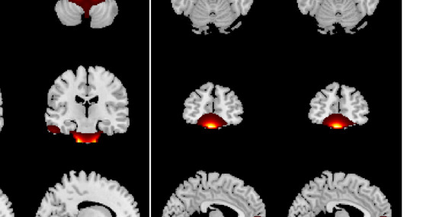

In the last two decades, unsupervised latent variable models---blind source separation (BSS) especially---have enjoyed a strong reputation for the interpretable features they produce. Seldom do these models combine the rich diversity of information available in multiple datasets. Multidatasets, on the other hand, yield joint solutions otherwise unavailable in isolation, with a potential for pivotal insights into complex systems. To take advantage of the complex multidimensional subspace structures that capture underlying modes of shared and unique variability across and within datasets, we present a direct, principled approach to multidataset combination. We design a new method called multidataset independent subspace analysis (MISA) that leverages joint information from multiple heterogeneous datasets in a flexible and synergistic fashion. Methodological innovations exploiting the Kotz distribution for subspace modeling in conjunction with a novel combinatorial optimization for evasion of local minima enable MISA to produce a robust generalization of independent component analysis (ICA), independent vector analysis (IVA), and independent subspace analysis (ISA) in a single unified model. We highlight the utility of MISA for multimodal information fusion, including sample-poor regimes and low signal-to-noise ratio scenarios, promoting novel applications in both unimodal and multimodal brain imaging data.